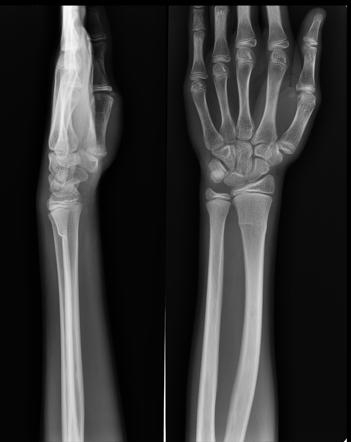

Greenstick Fracture - एका बाजूने फ्रॅक्चर, पण हाड वाकल्याने ते पूर्ण न तुटणे. हे फ्रॅक्चर लहान मुलांमध्ये जास्त आढळून येते कारण त्यांची हाडे लवचिक असतात.

Hairline Fracture - अतिशय बारीक फ्रॅक्चर जे कधी कधी एक्स रे मधून दिसत नाही.

Longitudinal Fracture - हाडाच्या लांबीवर उभा तुकडा पडणे.

Oblique Fracture - हाडाच्या अक्षावर झालेले फ्रॅक्चर.

Spiral Fracture - हाडाच्या एखाद्या भागाला पीळ पडणे.

Torus Fracture - यात हाड तुटत नाही पण हाडाचा आकार बदलल्याने वेदना होतात.

Transverse Fracture - हाडाचा सरळ सरळ मध्यभागातून तुकडा पडणे.